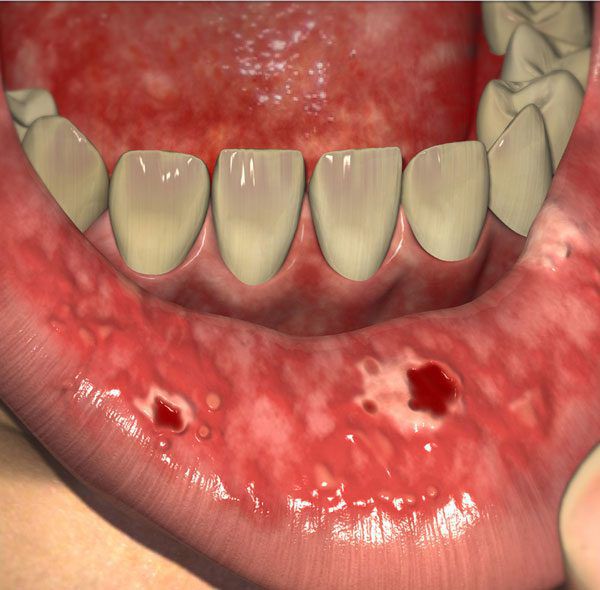

Начальными признаками являются покраснение и отечность слизистой оболочки мягкого неба, языка, губ и щек, которые появляются на 5-10 сутки от начала мукотоксической терапии. Поражение эпителиального слоя сопровождается зудом, жжением и субъективным дискомфортом при употреблении острой пищи. По мере прогрессирования заболевания очаги гиперемии замещаются беловатыми, приподнятыми над слизистой образованиями, начинается формирование язв. Пациент не может принимать твердую пищу из-за интенсивных болей. Тяжелый мукозит характеризуется обширными глубокими язвами, при которых больной не в состоянии употреблять даже жидкую пищу. При поражении других отделов ЖКТ возникают разлитые боли в животе, диспепсические расстройства: диарея, метеоризм, недержание кала.

Симптомы мукозита могут возникнуть через 1–2 недели после лучевой или химиотерапии [8] [28] . Первый признак мукозита — эритема (покраснение), затем на месте эритемы появляются эрозии и язвы.

![Язва в полости рта [25]](/pimg3/mukozit-prichini-simptomi-C58C6B.jpeg)